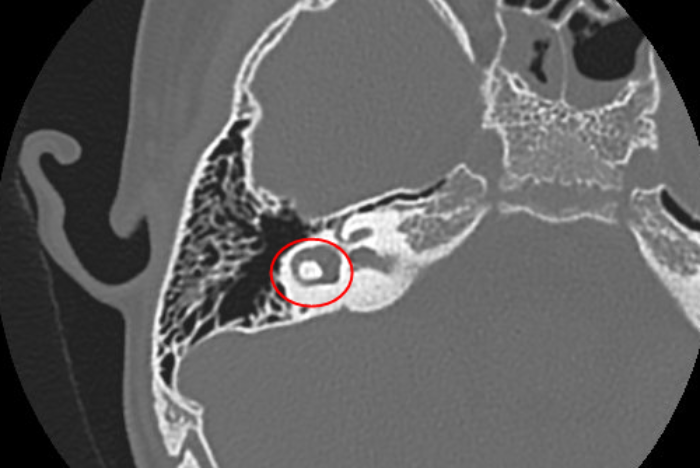

Tại đây, bệnh nhi được chụp cát lớp vi tính xương thái dương thấy hình ảnh khối u vị trí mặt trong chuỗi xương con. Đây là một bệnh lý hiếm gặp, có thể gây biến chứng nguy hiểm và ảnh hưởng đến chức năng nghe của trẻ nếu không được phẫu thuật điều trị kịp thời.